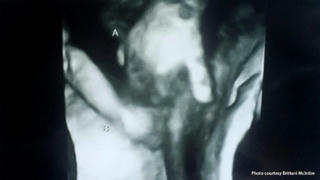

Cặp vợ chồng anh Ian McIntire và chị Brittani McIntire đang chờ đợi sự ra đời của cặp song sinh khác trứng Mason và Madilyn. Tuy nhiên, không may là các bác sĩ thông báo chỉ một bé có thể sống sót.